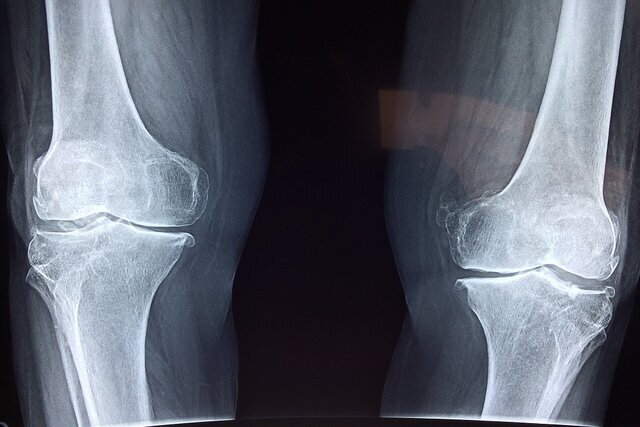

وی اظهار داشت: استئوپروز به‌طور عمده با کاهش تراکم معدنی استخوان تعریف می‌شود و در سنین بالا، به‌ویژه در زنان پس از یائسگی، می‌تواند منجر به شکستگی‌های زودرس شود. بر اساس شواهد موجود، از هر دو زن و از هر چهار مرد بالای ۵۰ سال، یک نفر دچار شکستگی ناشی از پوکی استخوان می‌شود. شکستگی‌هایی که معمولاً در نواحی گردن استخوان ران، ستون مهره‌ها و مچ دست رخ می‌دهند، ممکن است نخستین علامت این بیماری خاموش باشند.